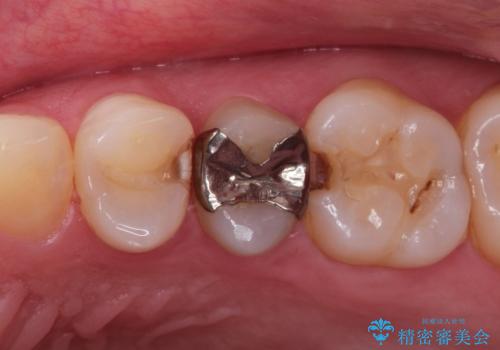

昔の詰め物のなかで広がる虫歯。セラミックインレー

- 詰め物が取れたことを主訴に来院されました。

古い材料を除去すると中で虫歯が進行していたため、顕微鏡下で虫歯を除去した後セラミックインレー、PGAインレーにて修復治療を行いました。